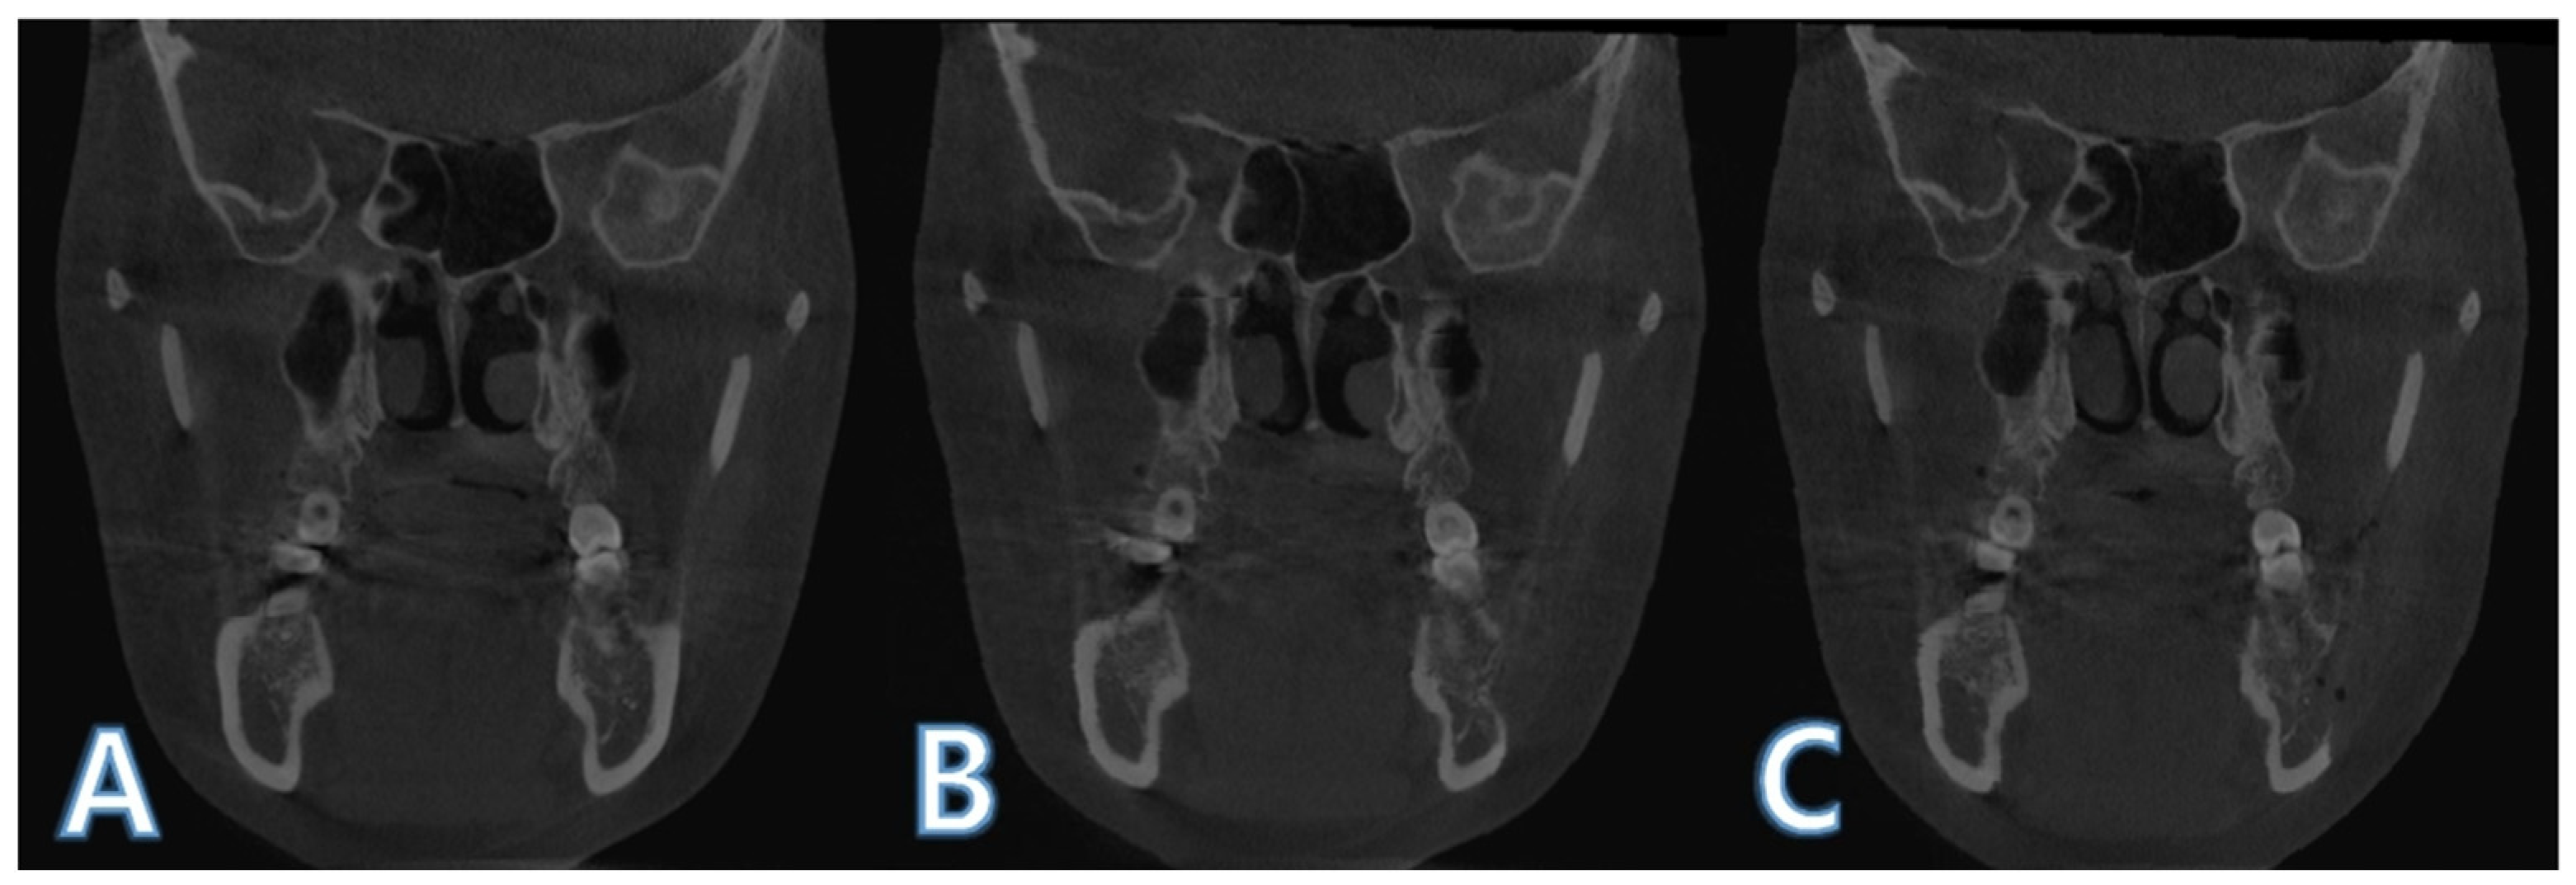

2.2. Boundary Selection of Region of Interest and Mandible Segmentation

2.3. Intensity-Based Registsration Using Segmented Mandible

2.4. Histogram Matching for Pixel Value Comparison

2.5. ROI Image Acquisition and Boundary Separation